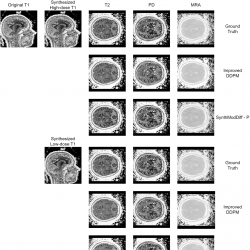

Fig. 2

Qualitative comparison of synthetic modality generation (T2, T1CE, and FLAIR) from a T1 input image on the BraTS2020 dataset. Columns from left to right show: input T1 image, synthesized target modalities. Rows from top to bottom show: ground truth, Improved DDPM, and the proposed SynthModDiff. Results are shown for both synthesized high-dose T1 (upper block) and synthesized low-dose T1 (lower block).

Figures

2 and

3 illustrate qualitative results for the task of synthetic modality generation from a single T1-weighted input image. In both figures, the first column shows the input T1 image, while the subsequent columns correspond to the synthesized target modalities, namely T2, T1CE, and FLAIR for BraTS2020 (Fig.

2), and T2, PD, and MRA for the IXI dataset (Fig.

3).

For each target modality, the first row represents the ground truth image acquired at the corresponding modality. The second and third rows present the synthesis results obtained using the second-best baseline method (Improved DDPM) and the proposed SynthModDiff method, respectively. This layout is repeated for two different input conditions: synthesized high-dose T1 (upper block) and synthesized low-dose T1 (lower block), allowing a direct comparison of robustness under varying noise levels.

As the dose level decreases, both methods exhibit some degradation due to increased noise in the input T1 image. However, Improved DDPM tends to produce overly smoothed results and fails to preserve modality-specific contrast, leading to blurred anatomical boundaries and reduced visibility of fine structures. In contrast, SynthModDiff consistently generates target modalities that are visually closer to the ground truth, preserving critical anatomical details and contrast patterns across different modalities. Notably, structures such as tissue boundaries, lesion regions, and vascular or bone-related details remain more distinguishable in SynthModDiff results, even under low-dose conditions.

These observations demonstrate that SynthModDiff is more robust for synthetic modality generation, particularly when the input modality is affected by reduced dose levels, which is crucial for practical clinical scenarios where minimizing radiation exposure is essential.